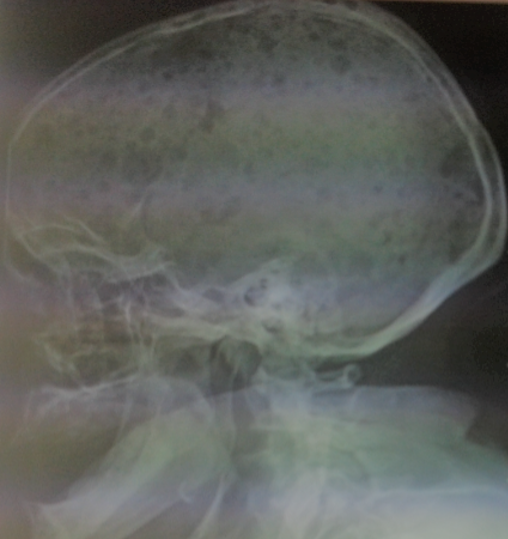

Il s'agit d'une patiente âgée de 54 ans, admise pour insuffisance rénale sévère. Elle a présenté une dyspnée stade II évoluant depuis un mois avec des douleurs thoraciques et douleurs osseuses associées à une anurie. L'examen clinique a retrouvé une hypertension à 160/80mmHg, un syndrome glomérulaire avec 2+ de protéine, 2+ de sang et une diurèse à 300cc. L'examen pleuro-pulmonaire a montré des rales crépitants basithoraciques bilatéraux. Sur le plan biologique, on a mis en évidence une insuffisance rénale sévère à 107mg de créatinine, urée à 1.65g/l,une hyperkaliémie à 7.8mmol/l, CRP à 78mg/l, une anémie normochrome normocytaire avec une Hb à 5.7g/dl et une hyperleucocytose à 13570 sans thrombopénie. Elle avait une hyperprotidémie à 144g/l, une normoalbuminémie à 33g/l, une hypercalcémie à 116g/l et une hyperphosphorémie à 120mg/l. L'électrophorèse des protéines sériques a objectivé un pic monoclonal de gammaglobulines à 60g/l avec à l'immuno-électrophorèse des protéines plasmatiques une gammapathie de type IgG kappa. La recherche de la protéine de Bence Jones était négative. Le myélogramme a montré une plasmocytose à 10%. Sur le plan radiologique, de multiples géodes à l'emporte pièce ont été visualisé sur la radiographie du crane de profil réalisant un aspect historique. La patiente a été mise sous protocole CDT1 à base de dexaméthazone, thalidomide 100mg et endoxan orale.